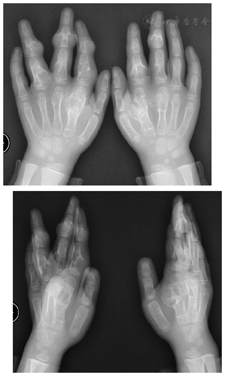

患儿,女性,6岁,因"发现双手多发肿物伴外观及功能障碍4年"来诊。4年前,家长发现患儿双手无痛性多发肿物,位于双手手背,左示、中、环指和右示、中指。曾经于当地医院行X光片检查,考虑"骨软骨瘤",未行特殊处理。后病情逐渐进展,并严重影响患儿手的外形及运动功能。患儿家族史阴性。查体发现:左手示中指环列和右手示中指列多处包块,大小不一,受累手指不同程度的偏斜畸形(图1)。肿物皮温正常,皮肤颜色无明显异常,触诊质硬,无压痛,无移动性,受累手指指间和掌指关节的主被动活动度受限。肢体其他部位未及明显肿物。

双手正斜位X光片显示:病变累及左手示、中、环指近节及中节指骨和第二、三掌骨,右手示、中指近节及中节指骨和第二、三掌骨,表现为类圆形囊状或膨胀性骨破坏,边界较清晰,病灶内密度不均,可见钙化影和骨性间隔,病灶不同程度累及骨骺,受累手指可见偏斜畸形,无病理性骨折。右桡骨远端亦可见类似病灶(图2)。